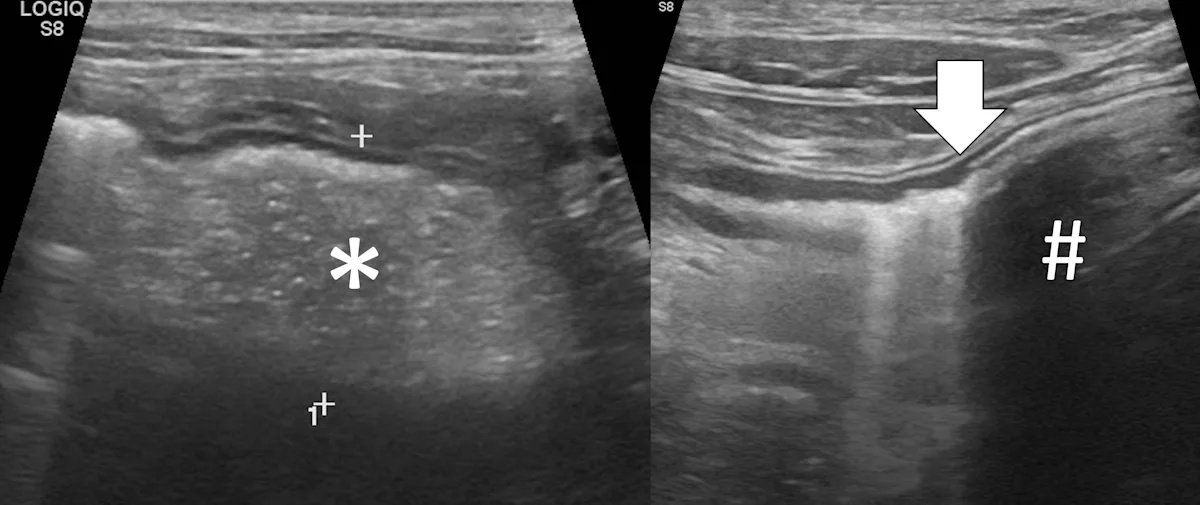

Pyloric outflow obstructions occur when a foreign body lodges in the pyloric outflow tract or the proximal duodenum and can cause variable gastric distention depending on the length of time the obstruction has occurred and whether the patient has recently vomited (Figure 2). Diagnosis of this type of obstruction via ultrasonography requires identification of an intraluminal structure that is causing gastric or proximal duodenal dilation orad to the foreign body.9-12 Foreign bodies are easier to see when surrounded by fluid. Although exceptions are possible, acute complete obstructions typically cause mild to moderate gas dilation, and chronic partial obstructions can cause more moderate to severe dilation, predominately with fluid.

FIGURE 2A

Abdominal ultrasound of a 3-year-old neutered male crossbreed dog with a surgically confirmed mechanical pyloric outflow obstruction. A homogeneously hypoechoic potato (asterisk) is present in the pylorus and completely visible due to its similar acoustic impedance as the surrounding soft tissues. There is transition from gas in the gastric lumen to the foreign body (white arrow). The remainder of the gastric lumen (pound sign) is not visible due to gas (black arrows) causing a hyperechoic surface with reverberation artifact.

Only the gastric wall located in the near field is visible if the stomach is filled with gas. The stomach may need to be evaluated from multiple angles, including subxiphoid, subchondral, right intercostal, and left intercostal. The pylorus shifts craniodorsally and is more difficult to see when the stomach enlarges and the patient is in dorsal recumbency. In these situations, the right intercostal approach can make finding the pylorus and proximal duodenum easier. Evaluating the stomach with the patient in different positions (eg, dorsal recumbency, lateral recumbency, standing) changes the distribution of fluid and gas and may aid in foreign body detection. Gas within the lumen of the stomach masks intraluminal structures; therefore, ultrasonography cannot rule out a gastric foreign body in a gas-dilated stomach.